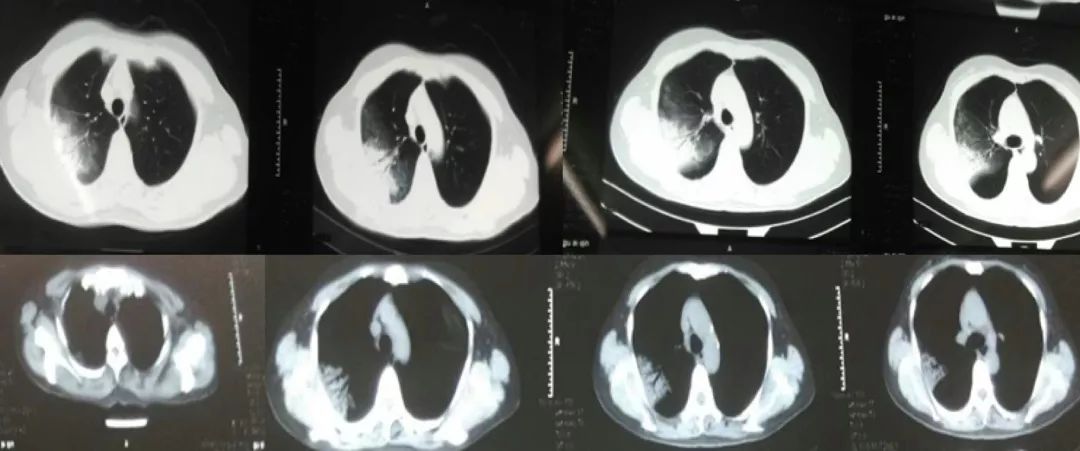

胸部CT:

2017-1-15

2017-1-23

2017-2-5

2017-3-5

患者起病时2017-1-15胸部CT病变主要在右肺上叶后段,表现为大片状高密度影,可见支气管气象,提示支气管内不是阻塞性病变,病灶内有实变,周围有渗出性改变,纵膈窗和肺窗差别比较大,说明病灶密度不是非常高;

2017-1-23胸部CT病灶从范围来看是逐步扩大的,仍可见支气管气象,周围渗出更加明显,纵膈窗来看病灶总体密度增高,影像学表现总体提示病灶进展;

2017-2-5胸部CT:整体病变范围与2017-1-23号CT变化不大,但整体密度呈减低趋势,纵膈窗影像密度与肺窗差别较大,说明病变呈好转趋势;

2017-3-5胸部CT右上肺大片状高密度影消散,仅留下少许高密度条索影,但左肺上叶后段出现新发病变,但与之前右肺上叶病变影像学特征有所不同,之前三次影像学病灶密度是比较均匀的,此次左肺上叶后段病变,除了实变之外可见类空洞样改变,仍有支气管充气征,周围见细条索影,右下肺背段见类结节影像。